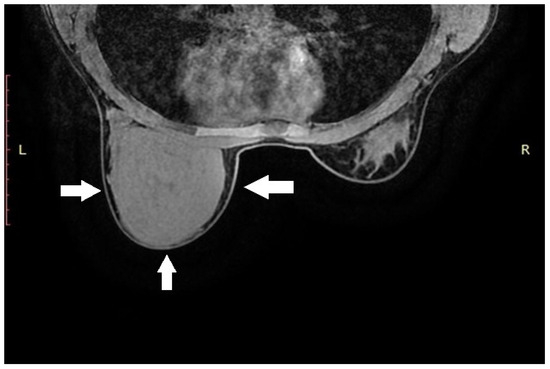

Background and Objectives: Optic disc drusen (ODD) can mimic papilledema and are linked to structural crowding, microvascular change, and visual-field loss. We synthesized structural/microvascular differences, functional status and change, diagnostic...